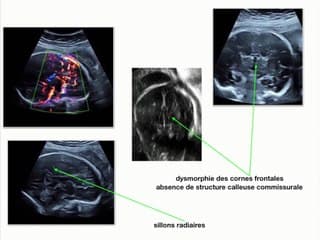

L'auteur contrairement à l'intitulé présente une belle observation d'une lissencéphalie avec une vallée sylvienne restant anormalement ouverte et qui a présenté l'intérêt d'attirer l'attention sur le développement anormal du cerveau fœtal. Introduction pédagogique dans le cadre difficile des lissencéphalies avec des étiologies complexes comme les mutations génétiques ou les infections à CMV.